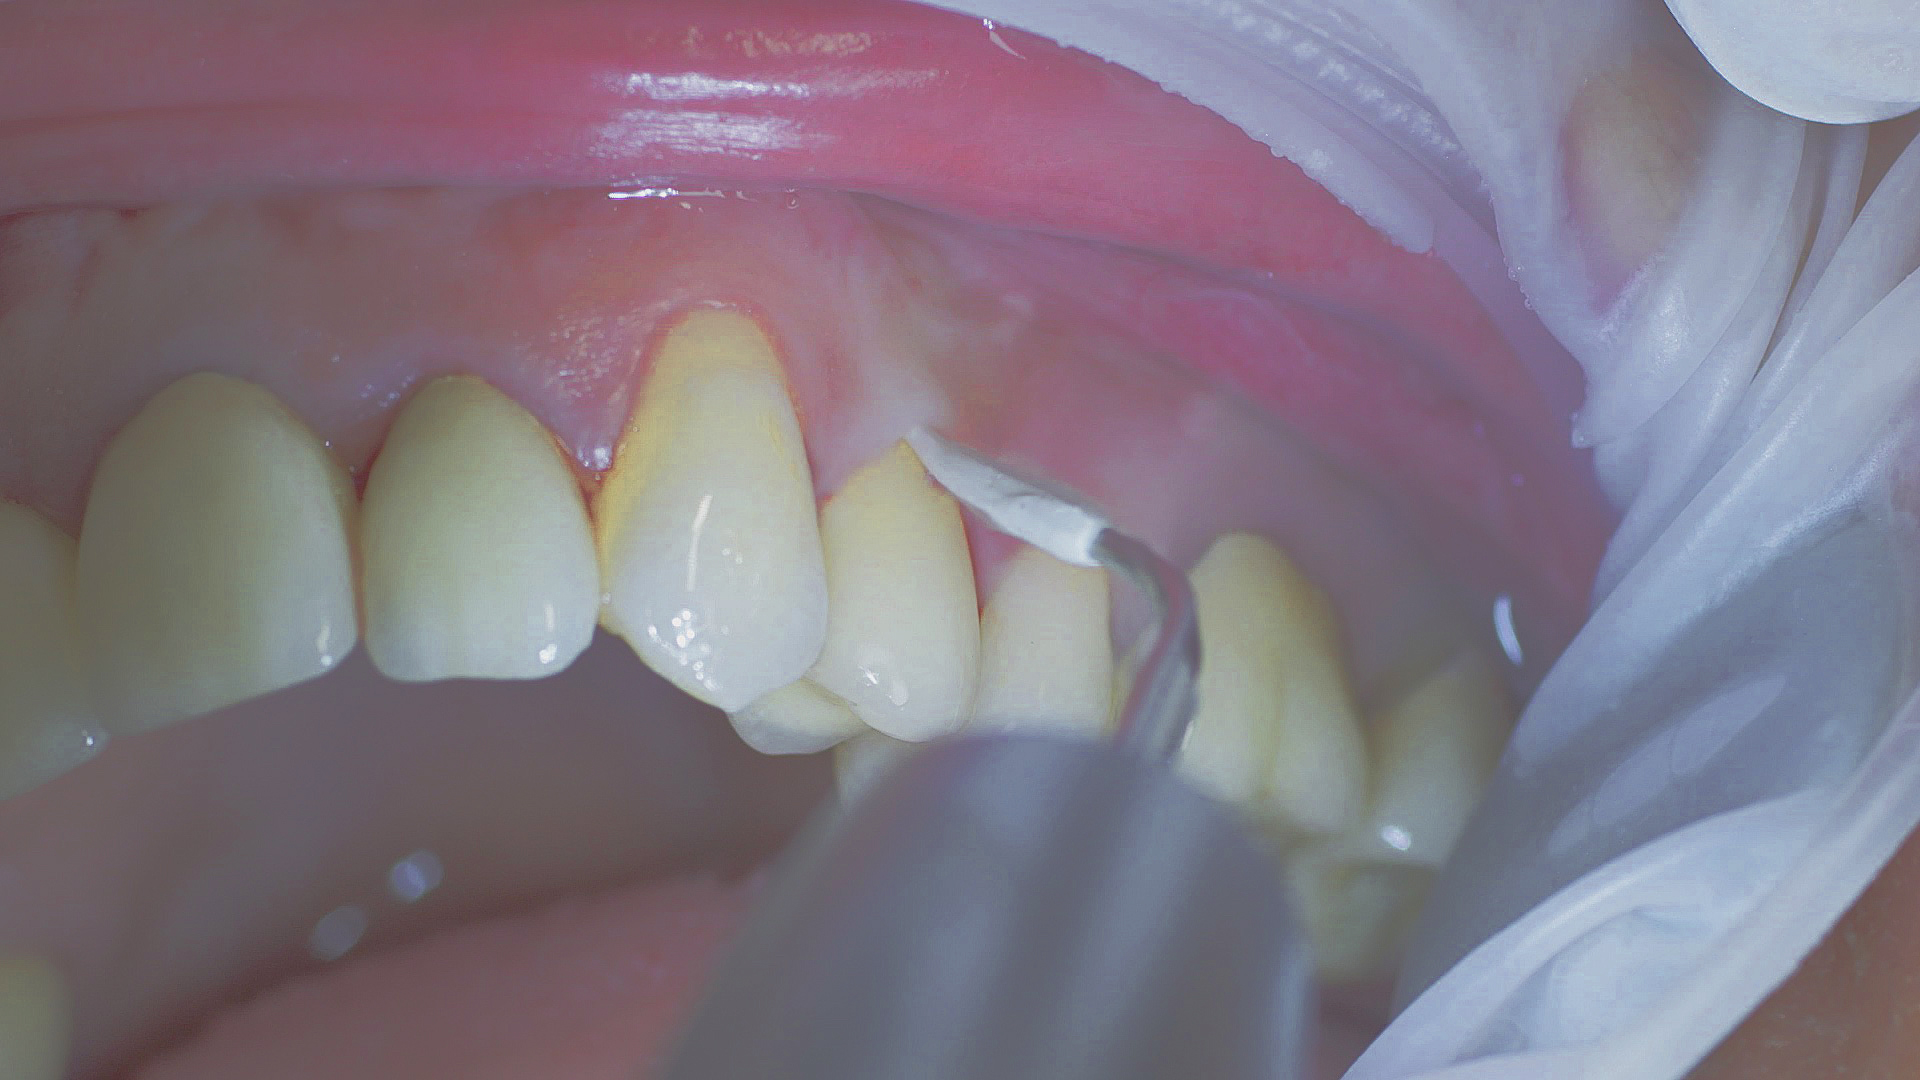

Removal of subgingival coatings (debridement) is carried out using sonic or ultrasonic devices and special periodontal tips as initial periodontal treatment (Fig. 3). Manual instruments can also be used. Further surgical and/or regenerative measures may be necessary, depending on the situation.